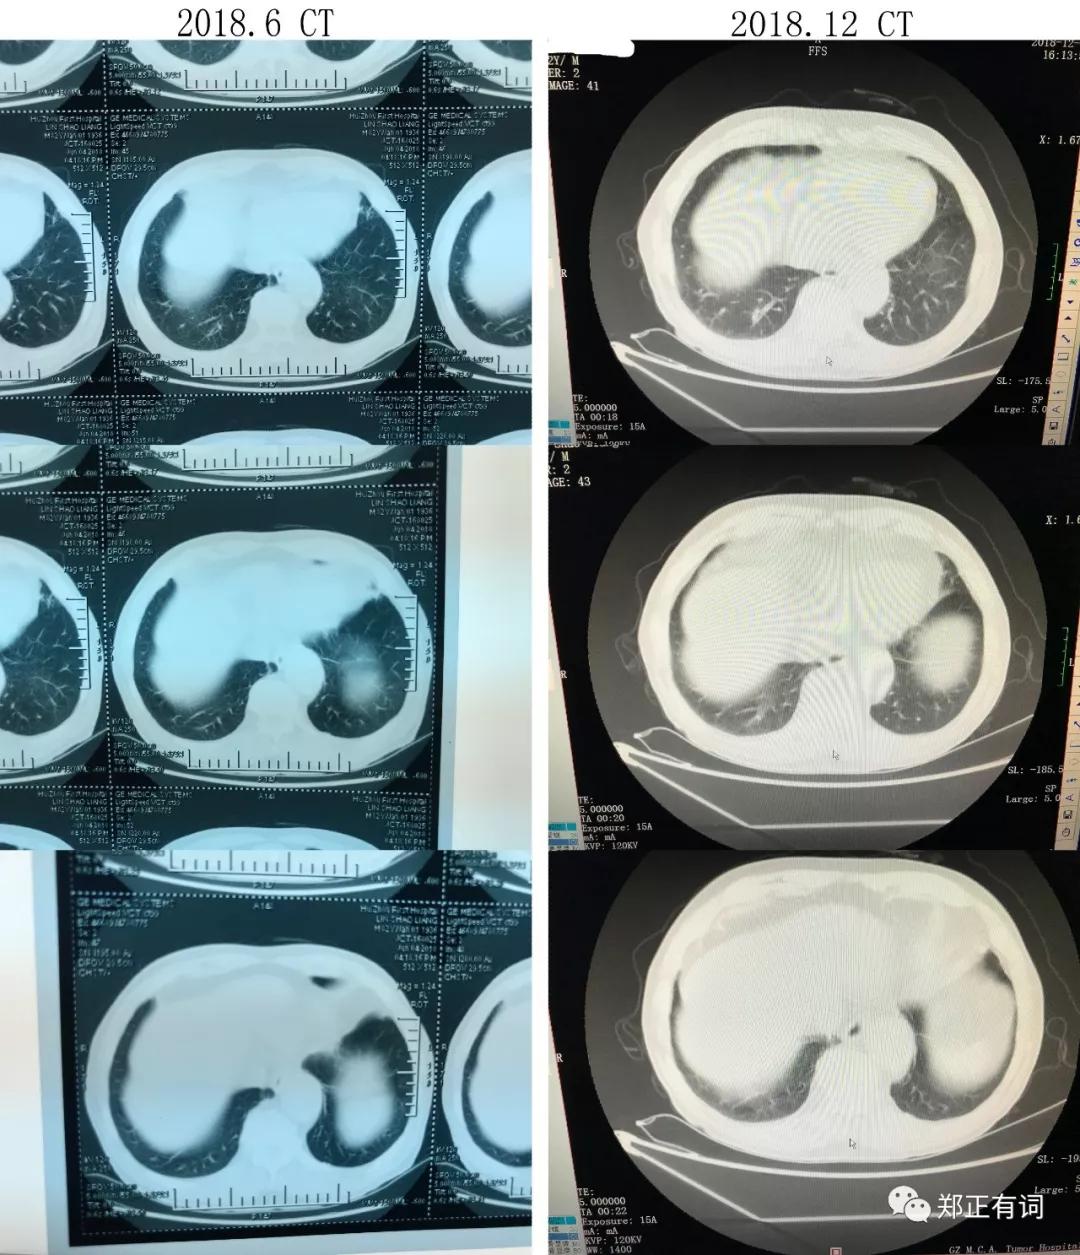

上面是2017.7~2018.11反复随访复查的CT片子。

可见,2017.7就诊时就在右上肺确切的看到异常病灶了,大小为17*15mm。

2018.6复查CT,提示病灶增大,大小为45*34mm。

而到了2018.11复查CT,提示病灶进一步扩大,大小为50*34mm。

于是,从2017.7开始,由着肿瘤生长,从当初最大径不足2cm,到现在最大径5cm。

这是纵隔窗的比较,

从中我们可以看出,早在2017.7,那个异常病灶已经有实性成分了;

在2017.7到2018.6期间,肺部病灶增大,而纵隔淋巴结并无显著差异;

2018.6到2018.11期间,伴随着肺部病灶的增大,出现了多发、多站的纵隔淋巴结肿大。

说明了什么?

说明了除了肿瘤本身在进展,纵隔淋巴结也出现转移了!

2017.7,临床分期 T1bN0M0 IA期

2018.6,临床分期 T2bN0M0 IIA期

2018.11,临床分期 T2bN2M0 IIIA期